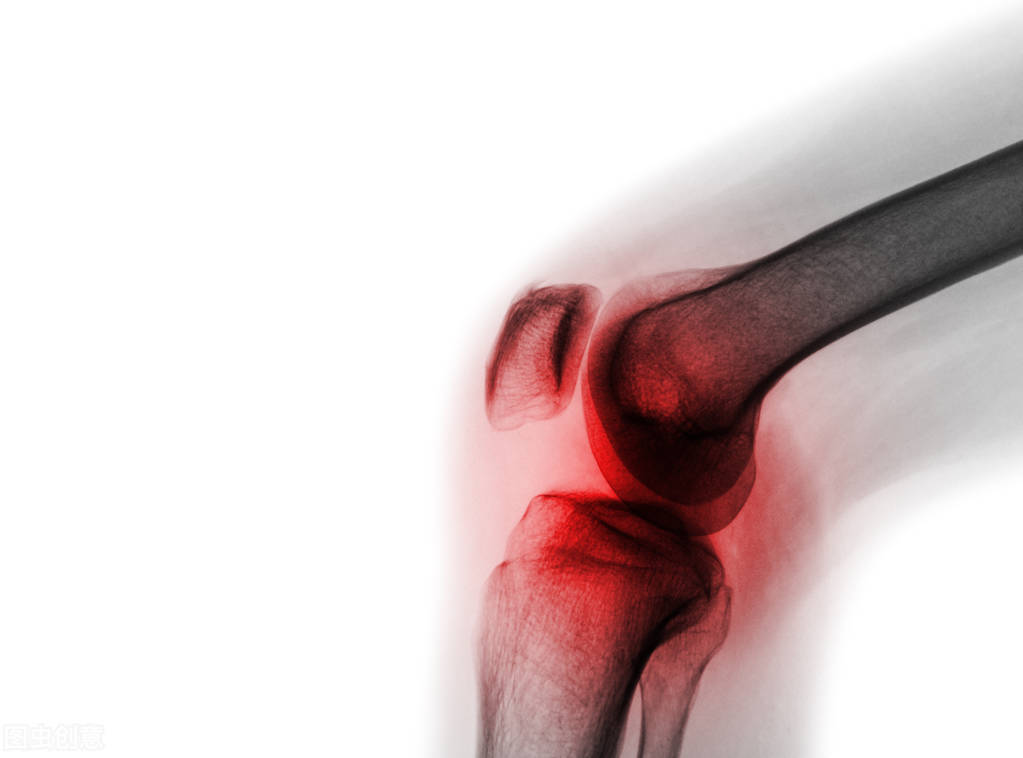

急性痛风的症状往往表现为关节出现红、肿、热、痛,发作时,一般大拇脚趾的第一趾关节,即大拇脚趾与脚掌的连接处会出现疼痛。但也可能发生于其他骨部位或关节处,如踝关节、脚背、膝关节、肘关节、腕关节、指关节等,主要是由于肢体末端血液循环较差,单钠尿酸盐容易在肢体末端沉积。此外,急性痛风发作可伴有头痛和发热。